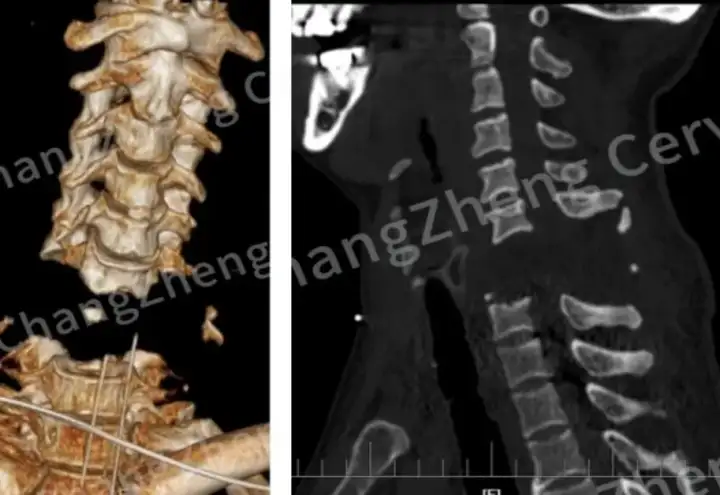

До операции у пациента несколько раз происходила остановка сердца, а нижние конечности парализовало. Результаты КТ-сканирования показали, что шейный отдел позвоночника пострадавшего фактически разорван. Экспертная комиссия, которую оперативно собрал доктор Хуацзян, сравнила сложность лечения с подъёмом космонавта в космосе, поскольку позвоночная артерия пациента уже была повреждена и закупорена, что могло привести к массивному кровотечению во время операции.

Поэтому профессор Чэнь Хуацзян стал пионером метода «поэтапной репозиции и внутренней фиксации с помощью сателлитной пластины». Этот новый подход обеспечивает одномоментную переднюю репозицию шейного отдела позвоночника и восстановление полной стабильности у пострадавшего. Операция официально началась 18 июня в 13:00: после вскрытия и разделения мягких тканей на передней поверхности шейного отдела позвоночника было обнаружено большое скопление крови и отёк в области шеи.